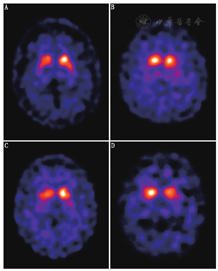

DAT结合显像剂功能的受损与多巴胺能神经元脱失之间的联系已被病理学证实[12]。由于PD以及各类aPS患者的DAT结合力减低,在DAT SPECT图像中可观察到脑基底节区放射性摄取的减少。但需注意的是,在一些aPS患者中上述基底节放射性非对称性减低可能并不明显,且从后壳核到尾状核的放射性浓聚梯度差异也不一定显著。图1为PD与各类aPS患者的DAT功能显像图。只要突触前多巴胺能神经元数量已发生变化,通过123I-FP-CIT SPECT诊断神经退行性PS的灵敏度一般高于95%[22]。

4.各类PS间的鉴别诊断。突触前功能显像在PD与aPS间、各类aPS之间(例如多系统萎缩、进行性核上性麻痹、皮质基底节变性)鉴别诊断方面的应用价值非常有限[39,40]。在图1中可看到,PD与aPS,以及各类aPS间的脑DAT SPECT图像表现无明显差异。一些其他的核医学分子影像技术在这方面可能更有优势,例如多巴胺能神经元突触后功能显像(D2受体显像)、脑葡萄糖代谢显像[41,42,43,44]。

由于PD和DLB在临床和病理上的关联非常密切,PDD和DLB在许多方面都有相似之处,可以预测二者多巴胺能神经通路应具有相似变化。在临床上的鉴别仅是粗略地基于"一年原则",即:痴呆在锥体外系症状至少1年后出现,倾向于诊断为PDD;若痴呆和锥体外系症状同时出现则倾向于诊断为DLB。通过尸检脑组织及放射性自显影证实,DLB患者纹状体的突触前多巴胺能配体的结合水平显著降低[67]。研究[4,68,69]表明,通过观察纹状体DAT结合力的改变可有效将DLB患者与阿尔茨海默痴呆症患者区分开来。和PD、aPS一样,DLB患者也以纹状体DAT结合力降低为主要特征,因此在123I-FP-CIT SPECT图像上可观察到基底节区放射性摄取的减低(图1)。而阿尔茨海默痴呆症患者的DAT结合力一般正常或仅有轻度减低。通过目视判读和定量分析脑123I-FP-CIT SPECT图像可准确评估纹状体DAT的功能状态,进而鉴别DLB和阿尔茨海默痴呆症患者,灵敏度可达80%,特异性为90%~94%[4,68,69]。最近一项整合了4个临床研究(包括419例患者)的Meta分析[70]表明,123I-FP-CIT SPECT鉴别诊断DLB和非DLB患者的灵敏度和特异性分别为86.5%和93.6%。DAT显像结果异常也似乎有助于将那些诊断不明的"可能的DLB"类别患者("possible DLB")归入为"很可能的DLB"类别("probable DLB")[71]。更具有说服力的证据来自于123I-FP-CIT活体显像和尸检结果的对比:DAT功能显像诊断DLB的灵敏度为88%(7/8)、特异性为100%(12/12);而临床诊断的灵敏度为75%、特异性为45%[72]。这些研究推动了将DAT显像列入DLB相关的共识诊断标准的进程。最近1篇综述[73]提到,尽管其他一些影像学技术在DLB和阿尔茨海默痴呆症的鉴别诊断方面也有所帮助:如DLB患者123I-MIBG SPECT显示其心肌放射性摄取减少,18F-FDG PET显示枕叶糖代谢的降低,MRI示内侧颞叶体积无异常改变等,但123I-FP-CIT SPECT显像仍是目前鉴别DLB与阿尔茨海默痴呆症最可靠有效的方法。需要注意的是,通过123I-FP-CIT SPECT来鉴别DLB和额颞叶痴呆(frontotemporal dementia)可能有一定局限性。研究[74]显示,有1/3(4/12)额颞叶痴呆患者也伴有DAT结合的减低。因此,若要进行此类鉴别诊断,还需进一步定量研究额颞叶痴呆患者脑多巴胺能神经元缺失与DLB和(或)PDD相比是否有程度上的差异。